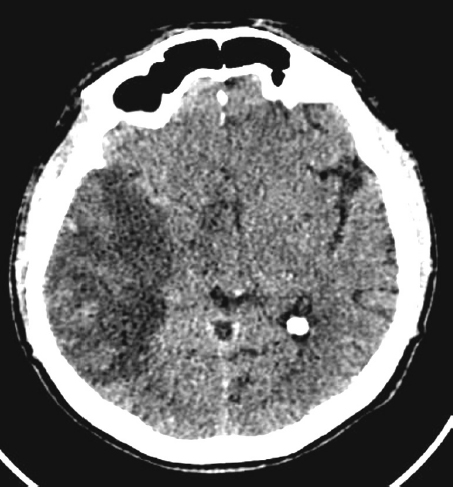

Clinical Case 1: a 63-year-old man with a mine-blast injury and shrapnel gunshot wounds to the head, neck, chest, abdomen, and extremities:

- Ischemic stroke in the territory of the right middle cerebral artery (from the time of injury) due to arterioarterial embolism, with development of left-sided hemiparesis and left homonymous hemianopia (Fig. 5);

Fig. 5. Computed tomography of the head. Signs of cerebral infarction (extensive hypodense area) in the right middle cerebral artery. Midline shift to the left by 6 mm.